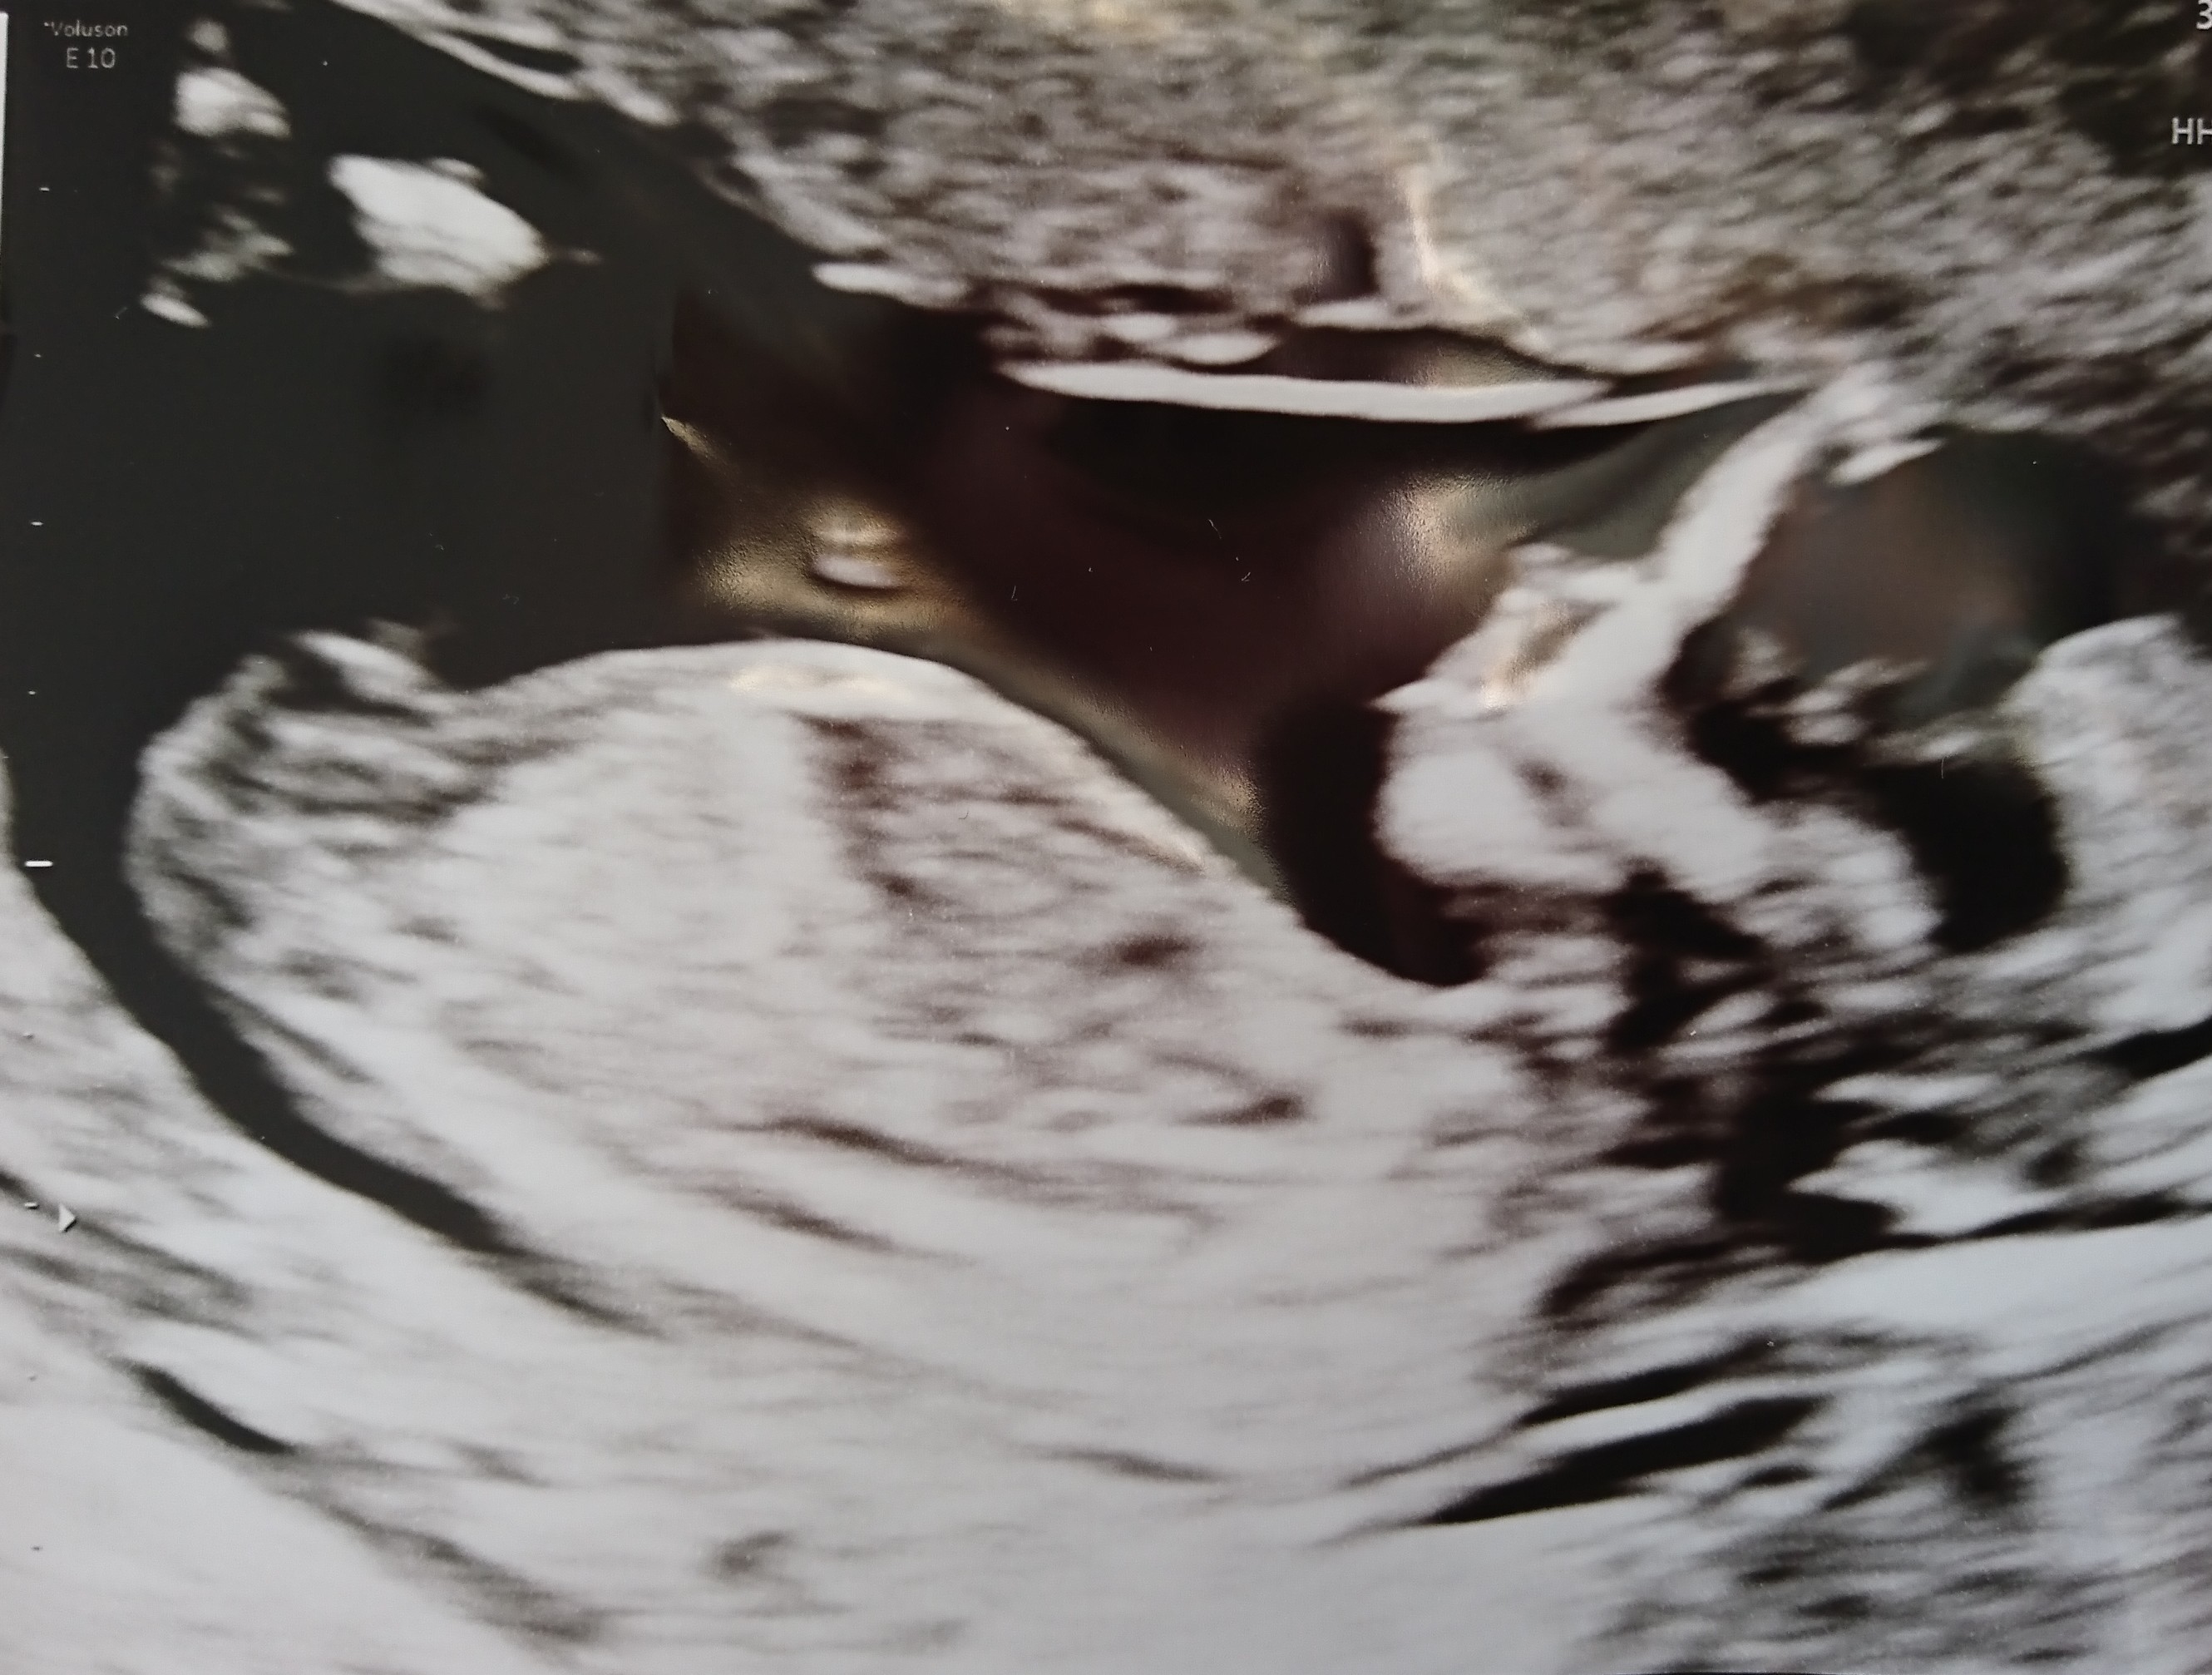

Hi Ladies. Here is pictures from my NT scan at 13 weeks.

I have been looking at many confirmed nub pictures. I am confused because it look boyish and girlish to me. It also did during my scan. At some point it looked boyish, but I saw a forknub that made me think girl. Do you think it looks like a boy or girl? :nails:

Attachment 41161Attachment 41160